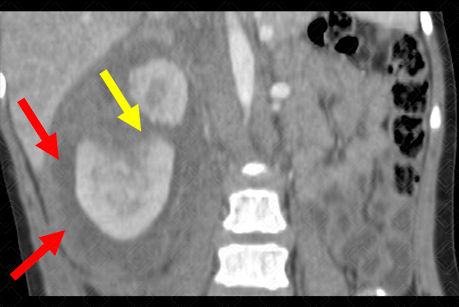

Texto alternativo para a imagem Figura 1. Créditos: Dra. Elazir Mota - Rio de Janeiro/RJ

Descrição da figura 1: Tomografia computadorizada do abdome com contraste na fase arterial. Presença de hematoma subcapsular (seta vermelha) e laceração no terço superior do rim direito (seta amarela).

• Grau II: Lacerações maiores através do córtex e estendendo para medula renal ou sistema coletor, com ou sem urinoma ou infarto segmentar (f iguras 1 e 2);